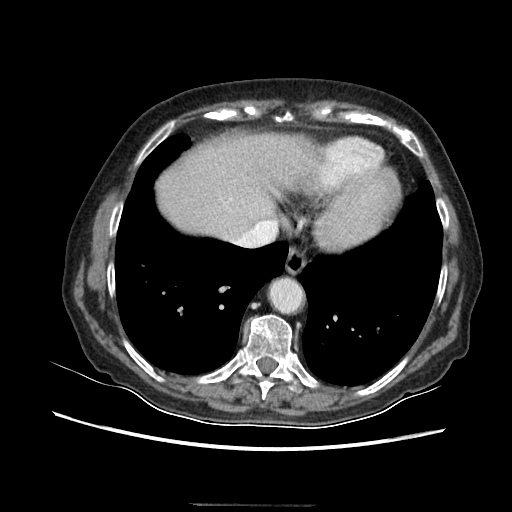

Original VENOUS CT scan

Full window (WL 1023.5, WW 4095 β†’ Low βˆ’1024, High +3071)

Generated VENOUS CT scan (A→B translation)